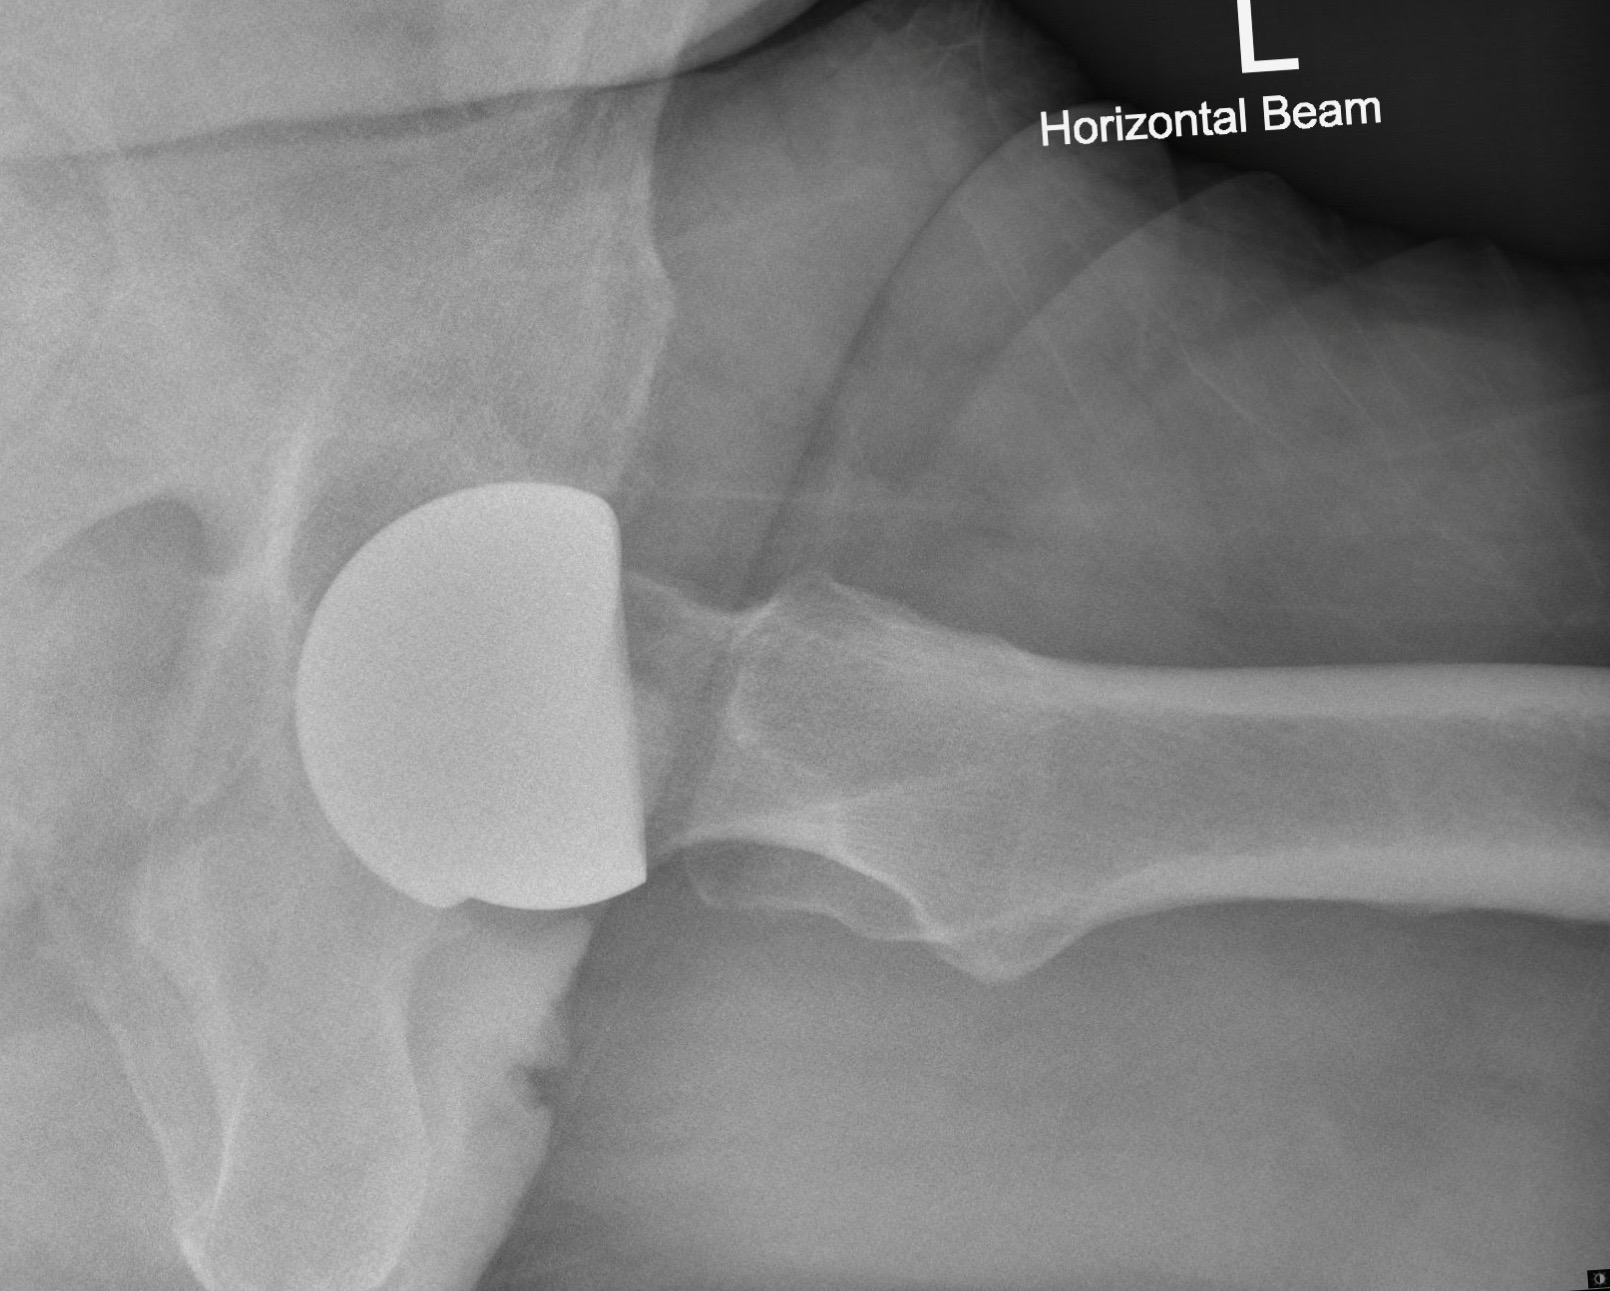

At the time of surgery, via a standard posterior approach, using exactly the same exposure and release as required for a metal-on-metal hip resurfacing, a ReCerf® device was implanted. The 56mm colour-coded socket was implanted using a specifically designed acetabular insertion device, used alongside the standard ADEPT® socket insertion handle and alignment jig. Socket position was targeted at between 35 and 40 degrees of abduction with anteversion matching the native socket and the transverse acetabular ligament, typically around 15 degrees.

The standard ADEPT® medial referencing jig was used to position a guide wire into the femoral head and neck, determining bone preparation and component position. Again, the same instrumentation used for the ADEPT® device is used with ReCerf®. With preparation complete, a compatible and similarly colour-coded 50mm femoral component was cemented in place, using standard cement fixation and impaction technique to the established ADEPT® metal-on-metal device. (As such the ReCerf® concept uses of the majority of the ADEPT® metal-on-metal instrumentation and would therefore provide the surgeon with the opportunity to determine bearing surface material with flexibility intraoperatively.)